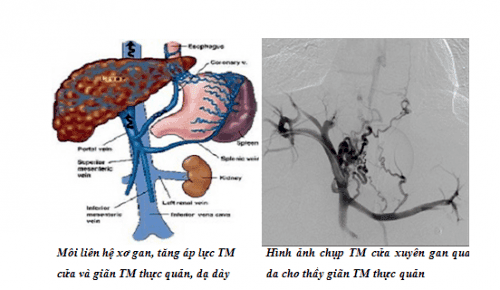

Chụp số hóa xóa nền và gây tắc búi giãn tĩnh mạch thực quản qua da là một thủ thuật can thiệp nội mạch. Dưới màn hình tăng sáng, vị trí giãn tĩnh mạch thực quản có thể đã vỡ hay chưa vỡ sẽ được tiếp cận và bơm vật liệu gây thuyên tắc nội mạch. Nhờ đó, dòng máu bị ngăn cách lưu thông, hiện tượng chảy máu sẽ được ngăn chạy hoặc giảm sức căng của búi giãn tĩnh mạch nên giảm được nguy cơ vỡ.

Để mở đường vào tĩnh mạch cửa, bác sĩ sẽ gây tê tại chỗ, rạch da. Bộ kim chọc siêu nhỏ với kích thước là 21G sẽ được chọc vào nhánh phải tĩnh mạch cửa trong gan, thường là nhánh ở hạ phân thùy V, VI. Một ống có kích thước 6F sẽ được đặt vào lòng mạch. Kế đến, bác sĩ sẽ chụp mạch đánh giá tổn thương bằng cách đưa ống thông Cobra và dây dẫn vào tĩnh mạch mạc treo tràng trên.

Sau đó, ống thông Cobra sẽ được thay bằng ống thông chụp mạch có đầu cong dạng đuôi lợn và có vị trí ở trong tĩnh mạch mạc treo tràng trên, ngay dưới vị trí hợp lưu với tĩnh mạch lách. Lúc này, bằng cách chụp số hóa xóa nền, hệ thống tĩnh mạch cửa ngoài và trong gan sẽ hiện lên khi bơm thuốc cản quang. Dưới màn hình huỳnh quang, bác sĩ sẽ đánh giá được hệ thống các nhánh bàng hệ và búi tĩnh mạch thực quản giãn đang vỡ gây chảy máu vào đường tiêu hóa trên.

Khi vị trí tổn thương đã được quan sát thấy, bác sĩ sẽ tiếp cận bằng cách dùng ống thông Cobra lựa chọn gốc của búi tĩnh mạch thực quản giãn. Một vi ống thông sẽ được đưa tiếp theo vào búi tĩnh mạch thực quản giãn qua ống thông Cobra để chụp mạch siêu chọn lọc qua vi ống thông nhằm xác nhận tình trạng búi tĩnh mạch giãn như thế nào và miệng vỡ gây chảy máu.

Tại đây, bác sĩ tiến hành can thiệp điều trị tắc búi tĩnh mạch thực quản giãn bằng vật liệu là vòng xoắn kim loại hoặc keo sinh học. Khi vật liệu được bơm vào vị trí tĩnh mạch giãn vỡ, dòng chảy sẽ được cầm lại và chấm dứt. Tuy nhiên, trước khi kết thúc, bác sĩ cần đánh giá sau can thiệp bằng cách thay ống thông Cobra bằng ống thông chụp mạch có đầu cong dạng đuôi lợn với đầu ống ở trong tĩnh mạch mạc treo tràng trên, ngay dưới vị trí hợp lưu tĩnh mạch lách.

Hệ thống tĩnh mạch cửa ngoài và trong gan lại một lần nữa được chụp số hóa xóa nền, các nhánh tĩnh mạch cửa trong và ngoài gan lưu thông bình thường, không có huyết khối. Đồng thời, bác sĩ cũng sẽ đánh giá hệ thống các nhánh bàng hệ và búi tĩnh mạch thực quản giãn, nhất là vị trí chảy máu đã được can thiệp bít tắc hoàn toàn, không còn thông thương tồn lưu với hệ thống tĩnh mạch cửa. Ngoài ra, siêu âm sơ bộ kiểm tra cũng không thấy tụ máu quanh gan, ổ bụng.